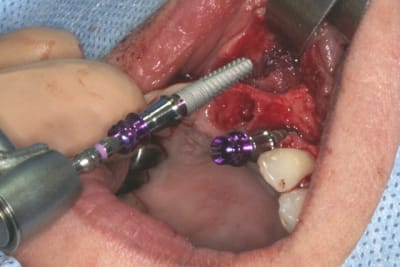

cet implant est une merveille!!!

connexion au top, pièces prothétiques aussi, facilité de pose incroyable...

tien, ce matin, extraction de 24/25, curetage méticuleux, forage, comblement du gap, pose des 2 implants qui se sont bloqués à 50Ncm au CA sur les 3 ou 4 mm apicaux, pose des vis de cicat, sutures...35min....tranquille...

si vous pensez que tous les systèmes se valent au niveau agrément chirurgical...

allez les vidéos